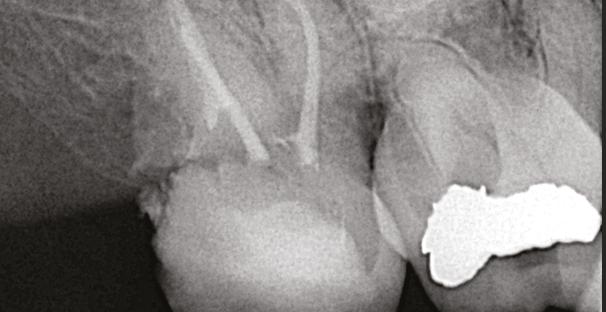

spacing of 3.4 mm between the two was noted (Figure 4). The recommended amount of space between a natural tooth and dental implant should be 1.5 mm-2 mm, proving adequate spacing in this case.15 Coronal views of the CBCT evaluation revealed a 6.1 mm x 3.0 mm hypodensity extending from the apical and distal aspect of tooth No. 11 (Figure 5A). Sagittal slices revealed the presence of healthy bone morphology between the distal border of the hypodensity on tooth No. 11 and implant No. 12, thus the hypodensity did not extend to the implant (Figure 5B). Reference was made to the Treatment Options for the Compromised Tooth: A Decision Guide published by the AAE in 2017 to determine prognosis.16 In evaluating the coronal tooth structure, tooth No. 11 had a well-fitting crown with adequate margins, no need for crown lengthening, and required only routine endodontic treatment placing it in the favorable category. The periodontal condition of tooth No. 11 was also favorable with probing depths equal to or less than 3 mm and a normal periodontium. Lastly, the apical periodontitis was expected to resolve following non-surgical root canal treatment.16 Thus, tooth No. 11 was diagnosed as pulpal necrosis with asymptomatic apical periodontitis with a favorable prognosis. Nonsurgical root canal treatment was planned, and informed consent was obtained.

6A-6D: 6A. Preoperative periapical radiograph of

proper working

radiograph of tooth No. 11 confirmed proper master cone

periapical radiograph of tooth No. 11 verified length control and appropriate obturation

Figure 4: Sagittal CBCT slice revealed 3.4 mm of space between the apex of tooth No. 11 and the mesial border of implant No. 12

Figures

slice

CBCT

tooth No. 11. 6B. Periapical radiograph of tooth No. 11 confirmed

length. 6C. Periapical

fit. 6D. Postoperative

USA, Savannah, Georgia) and gutta percha via continuous wave condensation. EndoSequence BC liner blue (Brasseler USA, Savannah, Georgia) was placed over the gutta percha at the canal orifice, and the tooth was temporized using a cotton pellet and Fuji IX placed in the access (Figure 6). Following completion of the root canal, the patient was scheduled for a 3-month reevaluation and referred to her provider for definitive restoration. Healing was observed at the 3- and 6-month postoperative visits. Periapical radiographs were exposed at each visit revealing bony healing (Figure 7). The patient reported no pain or symptoms following nonsurgical root canal treatment. At both visits, percussion and palpation were negative. A CBCT was captured at the 6-month postoperative exam to evaluate healing. Coronal CBCT slices revealed a reduction in lesion size to 3.5 mm x 1.6 mm. Sagittal slices also showed reduction in lesion and maintained health of bone surrounding implant No. 12 (Figure 8). A 2011 article by Ng outlines eleven factors that, if present, improve periapical healing following primary non-surgical root canal treatment.17 Only two of these eleven factors, absence of a preoperative periapical lesion and size of the preoperative periapical lesion, were not met in this case report. Along with this and the 2017 AAE Treatment Options for the Compromised Tooth: A Decision Guide article, the final prognosis for healing is favorable.16

Figures 7A-7C: 7A. Immediate postoperative periapical radiograph. 7B.Periapical radiograph of tooth No. 11 at the 3-month reevaluation showing a reduction in size of the periapical radiolucency. 7C. Periapical radiograph of tooth No. 11 at the 6-month reevaluation showing a further reduction in the size of the periapical radiolucency.

Figures 8A-8B: CBCT was taken at the 6-month postoperative visit. 8A. Coronal CBCT slices revealed a reduction in lesion size to 3.5 mm x 1.6 mm. 8B. Sagittal CBCT slices revealed a reduction in lesion size and maintained health of bone surrounding implant No. 12